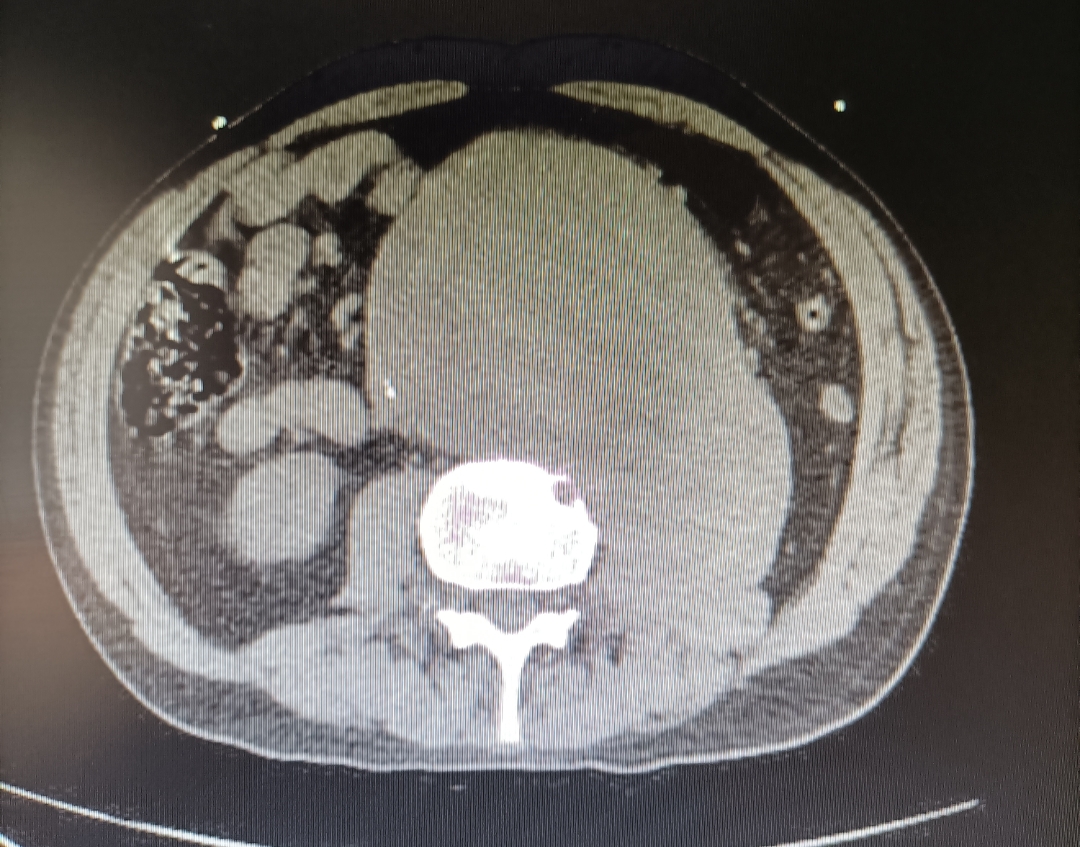

Se medica para control del dolor y se realiza Angio-TC de abdomen, donde se observan hallazgos compatibles con aneurisma de aorta abdominal infrarrenal de unos 14 x 13 cm que se extiende hasta bifurcación ilíacas, con calcificación intimal y trombo semilunar, con signos de rotura inminente.